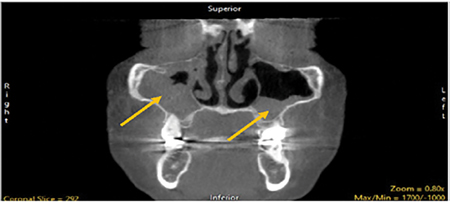

A year before her presentation, the patient presented to a board-certified otolaryngologist with complaints of persistent nasal congestion, sinus pressure, and difficulty sleeping. CBCT then demonstrated bilateral maxillary sinusitis with polyposis. (Fig. 1)

Fig. 1A

Fig. 1B

Upon presentation, 12 months after her surgery, cone-beam computed tomography (CBCT) scanning demonstrated mild improvement in the left-sided infiltrate but no change to the near-complete opacification of the right maxillary sinus, with obstruction of the ostia on that side. (Fig. 1B)